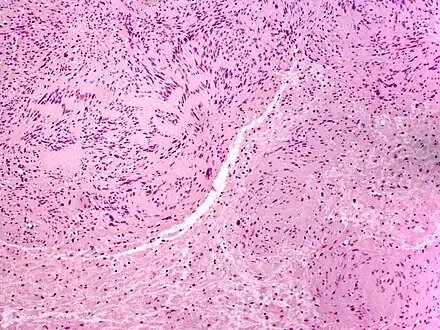

| Solitary circumscribed neuroma | |

A neuroma (/njʊəˈroʊmə/; plural: neuromata or neuromas) is a growth or tumor of nerve tissue.[1] Neuromas tend to be benign (i.e. not cancerous); many nerve tumors, including those that are commonly malignant, are nowadays referred to by other terms.

Neuromas can arise from different types of nervous tissue, including the nerve fibers and their myelin sheath, as in the case of genuine neoplasms (growths) like ganglioneuromas and neurinomas.

- Traumatic neuroma follows different forms of nerve injury (often as a result of surgery). They occur at the end of injured nerve fibres as a form of ineffective, unregulated nerve regeneration; it occurs most commonly near a scar, either superficially (skin, subcutaneous fat) or deep (e.g., after a cholecystectomy). They are often very painful. Synonyms include scar neuroma, amputation neuroma, or pseudoneuroma.